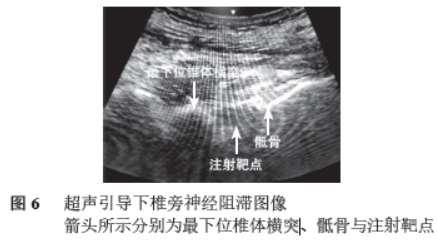

(见图2),显示S1 椎体腰椎化,S1~S2 椎间盘组织局限性向后突出压迫硬膜囊,诊断为 S1~S2 椎间盘疝。CT 三维重建(见图3),显示S1 椎体双侧横突肥大,与骶骨完全分离。经全脊柱X 线片证实无胸椎腰化,确诊为骶椎腰化(见图4)。2022 年4 月腰椎核磁共振 (magnetic resonance imaging, MRI),诊断为S1~S2 椎间盘疝(见图5)。再次超声引导下以S1 椎旁神经为目标神经根行阻滞治疗,每周1 次,连续3 周后症状逐渐缓解(见图6)。